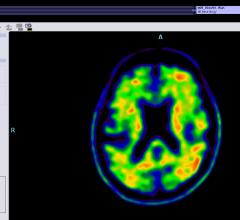

July 16, 2020 — Super-agers, or individuals whose cognitive skills are above the norm even at an advanced age, have been ...

July 14, 2020 — A new molecular imaging approach utilizing 18F-FDG positron emission tomography (PET) and magnetic ...